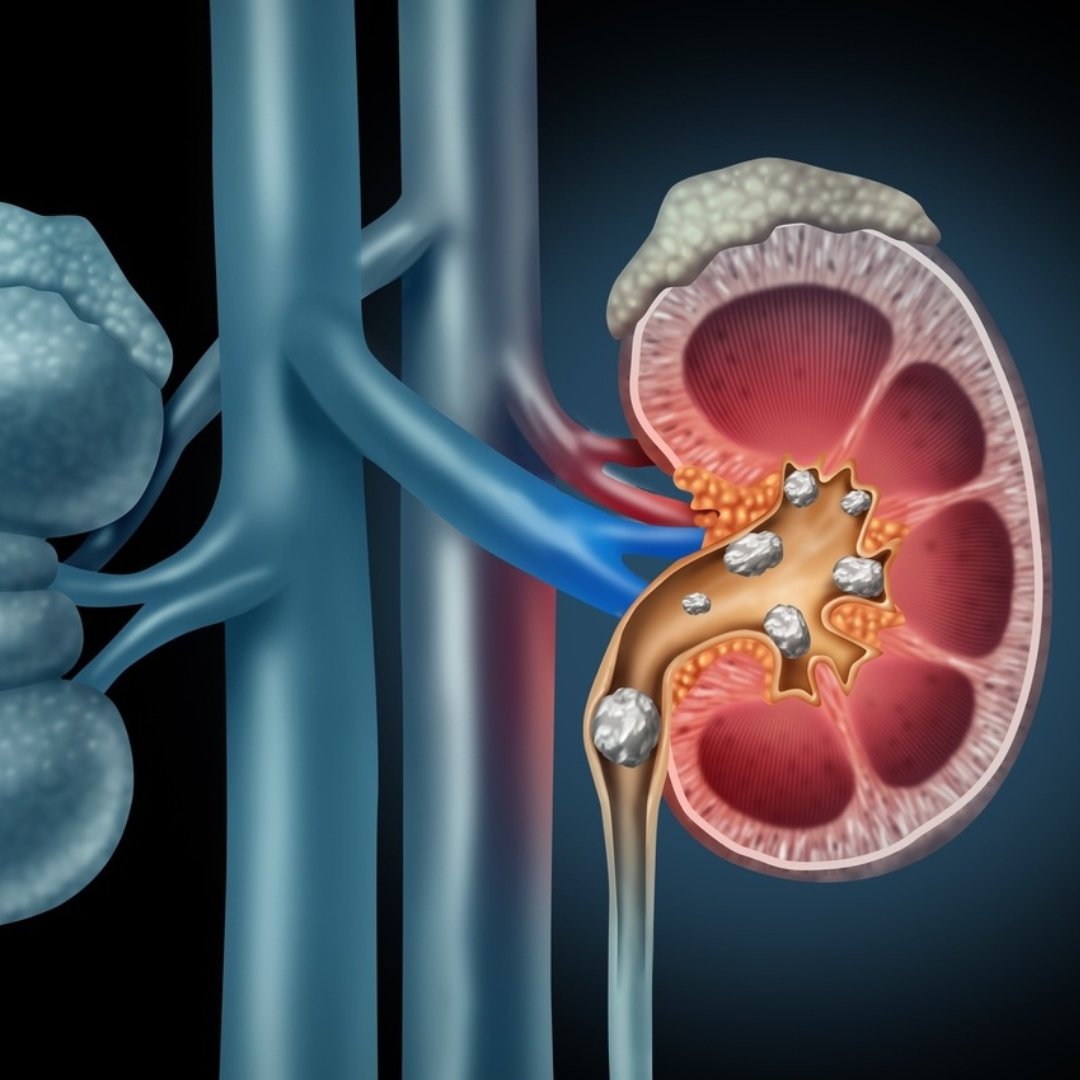

O cálculo renal (pedra no rim) é um problema de saúde muito comum, tratado cirurgicamente pelo urologista, de forma endourológica, isto é, sem cortes na pele.